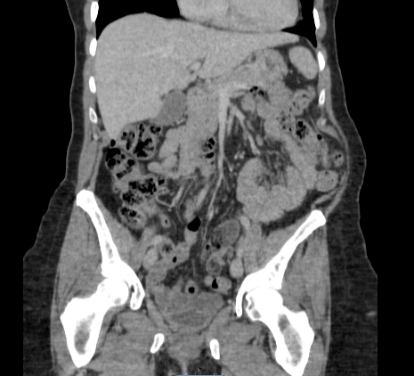

A 60-year-old female was assessed in pre op clinic for management of her symptomatic left lumbar incisional hernia. She presented with a lumbar bulge after surgery for scoliosis aged 17. The lumbar bulge could be reduced manually. Abdominal CT confirmed a left lumbar incisional hernia containing ascending colon, but no signs of obstruction or strangulation (Figure 1). During the consultation, a decision was made for an elective lumbar hernia repair. The patient provided consent for the anonymous publication of this case and accompanying images.

Figure 1: CT scan performed pre-operation (August 2016) showing left lumbar hernia.